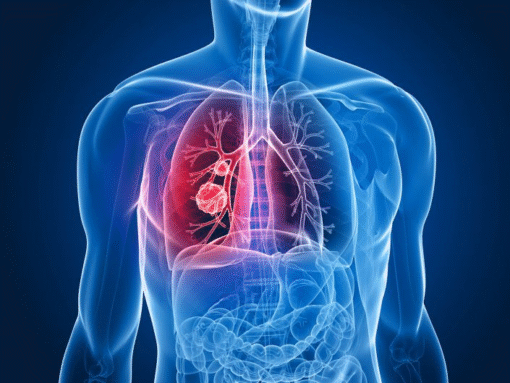

"🦟" /> BPCO: una crisi silenziosa che colpisce più di 2 milioni di argentini